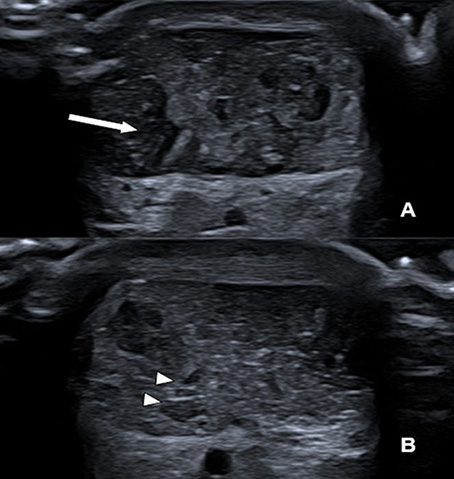

Throughout the tDCS sessions, Achilles’ tendon ultrasonography was performed, as shown in figure 4, in the axial plane. It revealed a partial tear involving the lateral and deep fibers in the tendon body, with the presence of interposed laminar fluid, and no evidence of a transfixing lesion. The control examination, performed after 30 days, showed the partial tear area filled by scar tissue, indicating evolution of the tissue repair process.

Figure 4. Serial Axial Ultrasonography of the Achilles’ Tendon

Initial Assessment (A): Axial view of the mid-portion of the Achilles tendon showing a focal area of hypoechogenicity involving the lateral and deep fibers, consistent with a partial-thickness tear. Note the presence of thin, anechoic laminar fluid (arrow) within the defect, with no evidence of complete fiber discontinuity. 30-Day Follow-up (B): The follow-up scan demonstrates significant structural remodeling. The previously identified hypoechoic defect is now filled with more organized, echogenic tissue, representing the formation of organized scar tissue and the resolution of the peritendinous fluid.